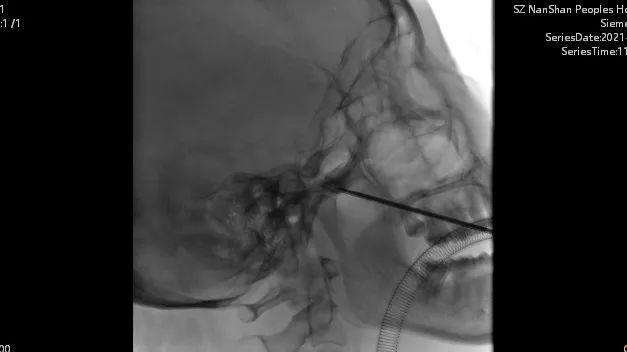

6月6日,在疼痛科主任熊东林的指导下,罗博士和团队顺利在李阿姨的颅内植入了一个神经起搏器,手术非常成功。

▲ 手术植入神经起博器